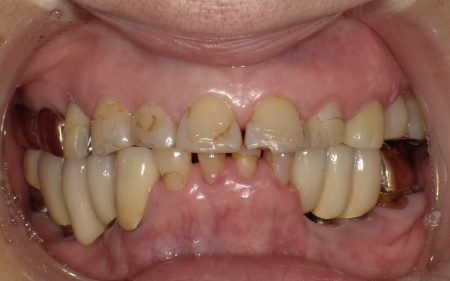

- 当院は、患者様の歯をできるだけ残し、長期的に再治療を防ぎ、質の高い健康を維持することを基本方針としています。

そのため「精密さ・耐久性・生体へのやさしさ」を重視した体制をとっており、原則として自由診療の治療をご提案しています。

一方、自由診療では個々の症例に合わせた治療設計、先進的な材料・技術の使用、再発予防を見据えた治療が可能です。